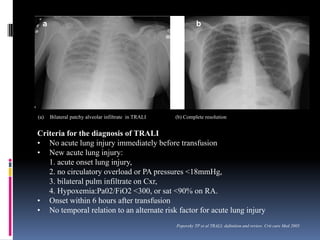

(a) Bilateral patchy alveolar infiltrate in TRALI (b) Complete resolution

a b

Criteria for the diagnosis of TRALI

• No acute lung injury immediately before transfusion

• New acute lung injury:

1. acute onset lung injury,

2. no circulatory overload or PA pressures <18mmHg,

3. bilateral pulm infiltrate on Cxr,

4. Hypoxemia:Pa02/FiO2 <300, or sat <90% on RA.

• Onset within 6 hours after transfusion

• No temporal relation to an alternate risk factor for acute lung injury

Popovsky TP et al TRALI; definition and review. Crit care Med 2005